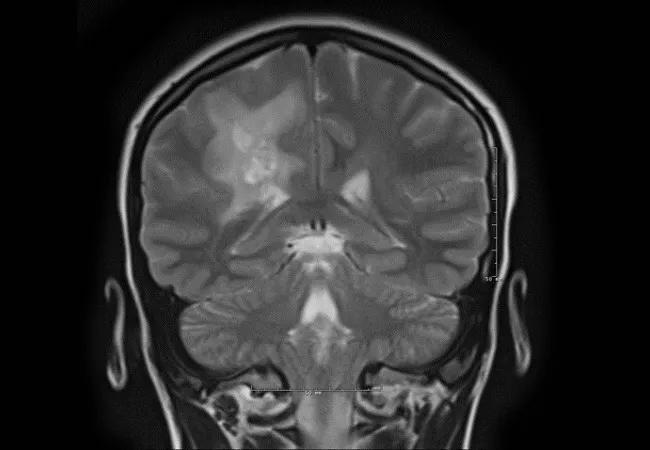

A previously healthy 14-year-old girl was seen for a second opinion at Cleveland Clinic after initially presenting for medical attention after findings of a mild left hemiplegia on clinical examination following evaluation of a sports-related knee injury. She also had problems with headache at this time. Brain MRI showed abnormal T2/FLAIR signal intensities in the deep white matter of the bilateral cerebral hemispheres, most prominent in the right parietal lobe, and demonstrated rim enhancement and surrounding edema (Figure).

Brain MRI images

Figure. Multiple T2 signal lesions in the deep white matter of the right parietal lobe with surrounding edema (top three images) and rim enhancement (bottom two images).